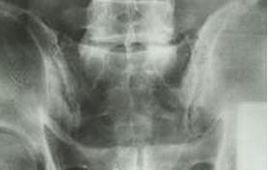

根據外傷史、臨床症狀及體徵,並參考X線片,可明確診斷。如經牽引手法聽到骶髂關節響聲後疼痛立即消失者可明確診斷。但需與腰骶關節扭傷和纖維環破裂症鑑別。